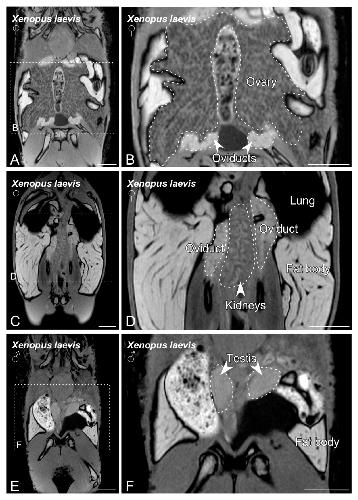

Sex Determination in Two Species of Anuran Amphibians by Magnetic Resonance Imaging and Ultrasound Techniques., Ruiz-Fernández MJ, Jiménez S, Fernández-Valle E, García-Real MI, Castejón D, Moreno N, Ardiaca M, Montesinos A, Ariza S, González-Soriano J., Animals (Basel). November 18, 2020; 10 (11):